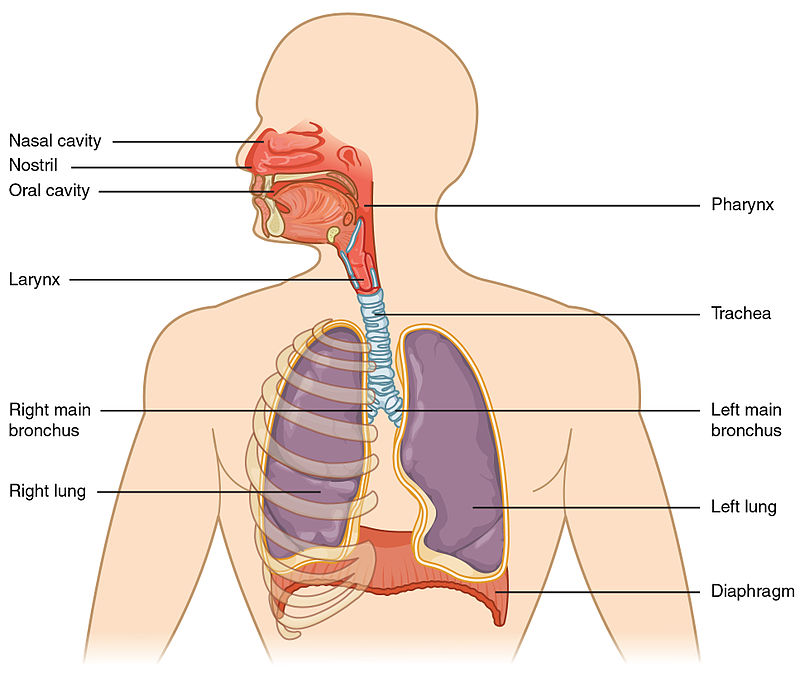

1 – Review of Respiratory System Anatomy